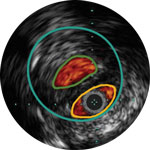

Die IVUS-Technologie von Philips liefert detaillierte Läsionsbilder, die Ihnen die Entscheidung über das optimale Vorgehen erleichtern.

Erleichtert die Dimensionierung des Geräts, um eine präzise Wandapposition, Medikamentengabe und Platzierung sicherzustellen

Verstehen Sie Art und Schweregrad der Plaque, um das richtige Gerät zu wählen

Visualisieren Sie die Position der Plaque für eine präzise Behandlung

Bestätigen Sie die Position des wahren Lumens oder des subintimalen Führungsdrahts